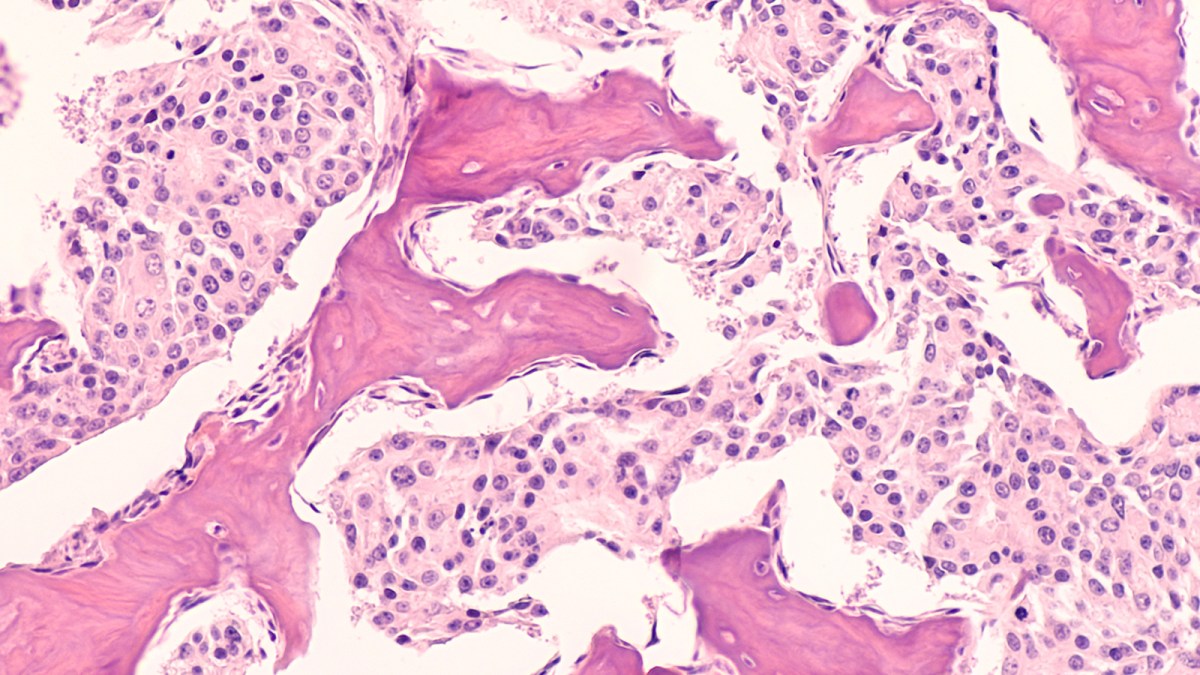

The new research, published in Nature Genetics, identified a cell membrane protein called NALCN that serves as a sodium ion channel and acts as a “key regulator” of metastasis. These channels control the flow of sodium into and out of the cell.

Removing or blocking NALCN activity in mice with cancer “markedly increased the number of circulating tumor cells (CTCs) and metastases,” the authors wrote in their paper.